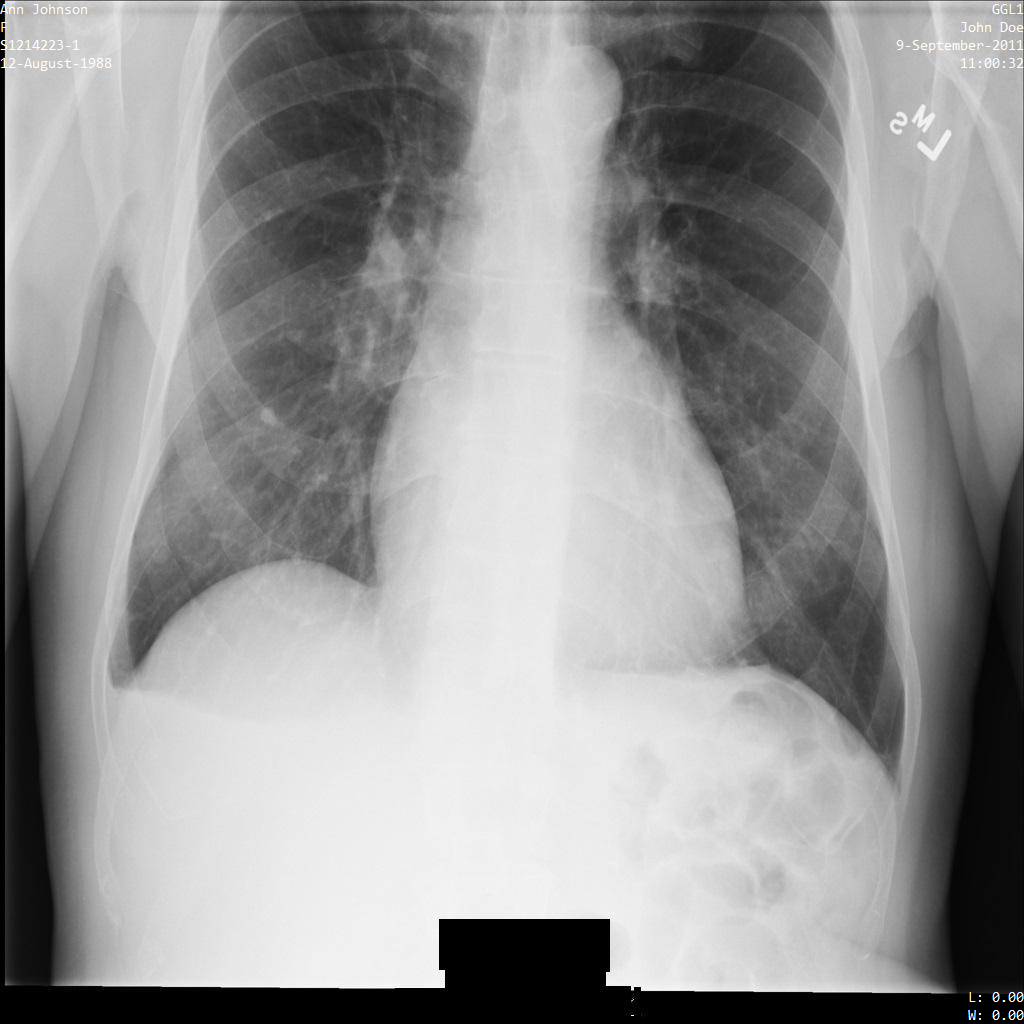

以下の各セクションでは、DICOM データを匿名化するさまざまな方法について、例を示しています。また、それぞれの例で匿名化された出力画像を示しています。各例では、入力として以下の元画像を使用しています。

各匿名化オペレーションからの出力イメージをこの元のイメージと比較して、オペレーションの効果を確認できます。

Cloud Healthcare API に画像を送信すると、画像は次のように表示されます。画像の上部隅に表示されているメタデータは削除されていますが、画像の下部にある焼き付き保護対象保健情報(PHI)は残ります。焼き付きテキストも削除するには、画像の焼き付きテキストを削除するをご覧ください。